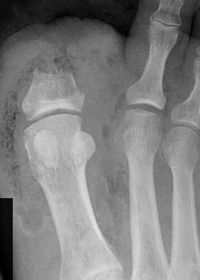

| Describe what is occurring at the head of the 3rd met | Freiberg’s infarction (avascular necrosis of the metatarsal head) |